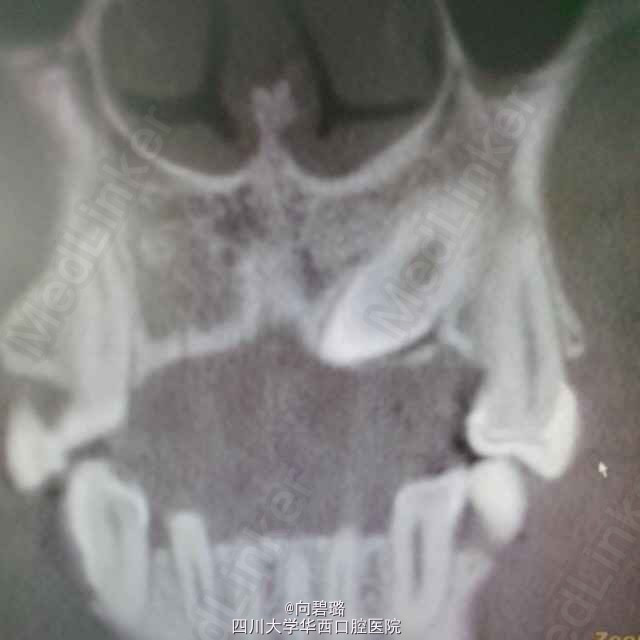

患者,男24岁左上颌乳牙滞留求治

63牙滞留,cbct示:23牙异位

23异位,拔除后行种植修复

尖牙异位还是比较常见的,我们定的方案是拔出后种植修复,不知道正畸能不能牵出?